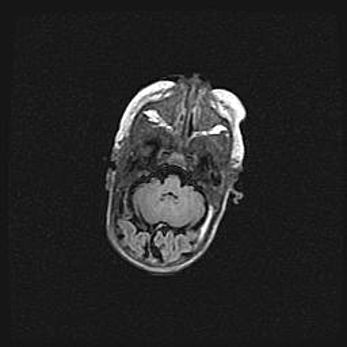

Лейкомаляция с кистозно-глиозной дегенерацией головного мозга.

Возраст: 2 месяца 25 дней

Вес: 6400 г

Окружность головы: 40 см

Срок гестации: 41 неделя

Лейкомаляцию относят к ишемически-гипоксическим повреждениям головного мозга, диагностируемым у новорожденных. При лейкомаляции в головном мозге обнаруживают очаги некроза, возникшие после тяжелой гипоксии и нарушения кровотока. В процессе морфогенеза очаги проходят три стадии: 1) развития некроза, 2) резорбции и 3) формирования глиозного рубца или кисты. Перивентрикулярная лейкомаляция (ПЛ) встречается примерно в 12% случаев среди новорожденных, обычно – у недоношенных детей, причем, частота ее зависит от массы, с которой младенец появился на свет. Наибольшее число малышей страдает лейкомаляцией, если масса при рождении 1500-2500 г.